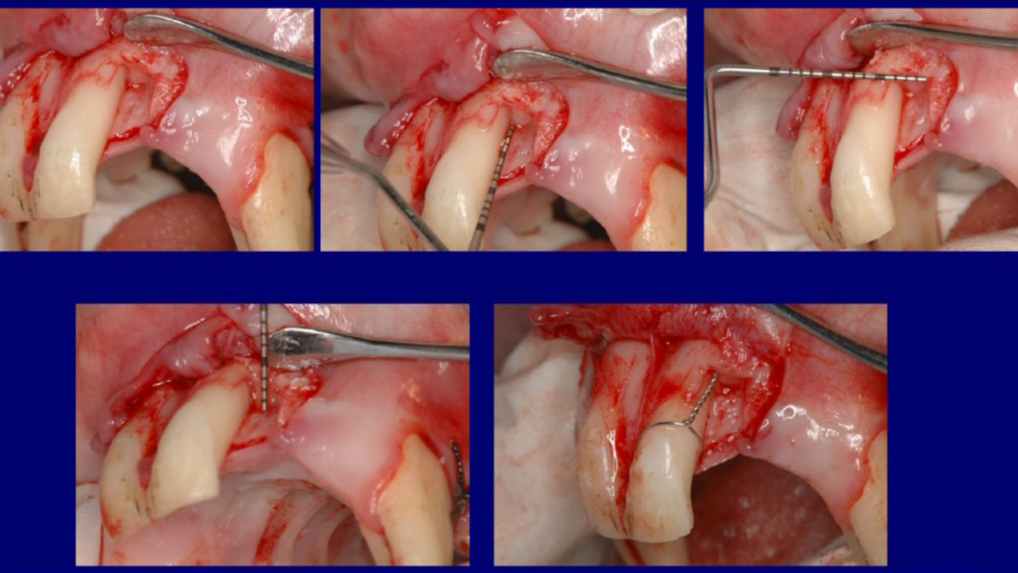

Increasing keratinized gingiva around upper implants using a strip gingival graft

Dr. Sascha A. JovanovicThis clinical video performed by Dr Jovanovic demonstrates the process of uncovering two maxillary dental implants with minimal to no keratinized gingiva and a shallow vest...